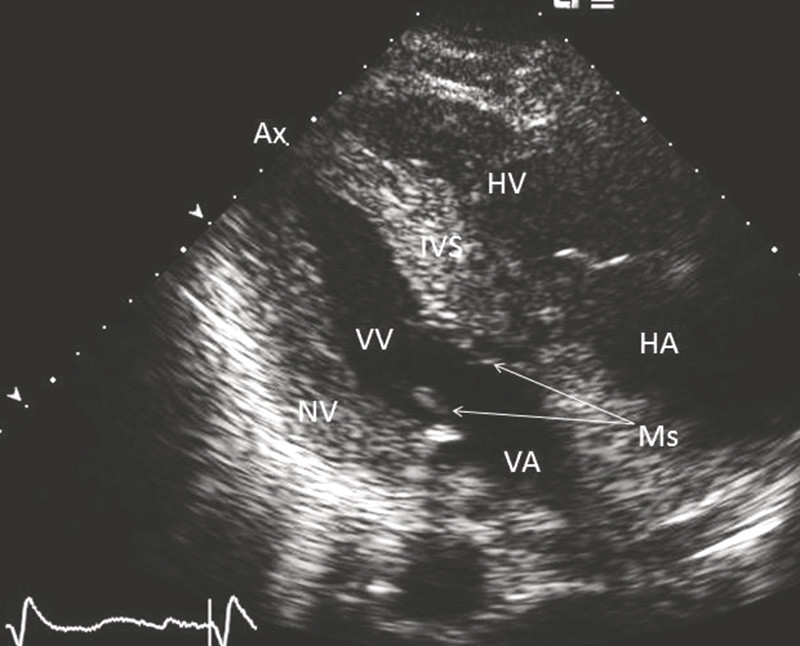

Vi undersøkte pasienten videre med ekkokardiografi. Det forelå ingen perikardvæskeansamling. Venstre ventrikkel var generelt tydelig hypertrofiert med veggtykkelser på 1,6 – 1,7 cm (normale veggtykkelser ≤ 1,1 cm) (fig 2). På grunn av hypertrofien hadde ventrikkelen liten kavitet med endediastolisk tverrdimensjon på 3,9 cm (normalområde 4,2 – 5,9 cm). Ventrikkelen viste hypernormal tverrkontraktilitet i alle avsnitt uten tegn til infarktsekvele, mens lengdekontraktiliteten var redusert. Ventrikkelens ejeksjonsfraksjon viste normal verdi på 65 %. Det forelå ingen systolisk intrakavitær avklemming i ventrikkelen. Mitralklaffen hadde noe fortykkede seil med god bevegelighet og en liten lekkasje.

Blodstrømshastigheter gjennom mitralklaffen og vevshastigheter ved mitralringene indikerte samlet forhøyet fyllingstrykk i venstre ventrikkel. Aortaklaffen var trikuspid med fortykkede kusper som viste ganske god åpningsbevegelighet, og det ble beregnet et åpningsareal på minst 1,5 cm². Ved dopplerundersøkelse ble middel-/maksimalgradienten over aortaklaffen målt til 10/17 mm Hg. Det forelå dessuten en minimal lekkasje i kommisurkontaktpunktet mellom de tre aortakuspene. Høyre ventrikkel hadde normale indre dimensjoner og viste god kontraktilitet. Vena cava inferior var imidlertid utvidet, og respiratoriske kalibervekslinger var redusert til bare 20 % under vanlig respirasjon. Dette indikerte forhøyet fyllingstrykk i høyre ventrikkel. Det forelå en trikuspidallekkasje av moderat størrelse. Maksimalgradienten over denne var 30 mm Hg, som tillagt et forhøyet høyre atrietrykk indikerte systolisk pulmonalarterietrykk på 40 – 45 mm Hg. Fri vegg på høyre ventrikkel målte 1,1 cm i tykkelse (normal tykkelse ≤ 0,5 cm). Pulmonalklaffen var normal. Begge atrier var moderat forstørrede. Atrieseptum var fortykket til 1,1 cm. Myokard i begge ventrikler ga et påfallende granulært uttrykk (fig 2).

Amyloidavleiring i hjertet disponerer for restriktiv kardiomyopati med utvikling av hjertesvikt. Ekkokardiografi er en tidlig og sentral undersøkelse ved vurdering av både årsaker til og grad av hjertesvikt. Karakteristiske funn ved hjerteamyloidose er biventrikulært fortykkede vegger med god ejeksjonsfraksjon (5, 6). Venstre ventrikkels kavitet har normale eller reduserte dimensjoner, og ved reduserte kavitetsdimensjoner (sekundært til vegghypertrofi) er ventrikkelen gjerne hyperkontraktil i tverraksen. Ventrikkelens kontraktilitet i lengdeaksen er derimot redusert allerede tidlig i sykdomsforløpet. Reduksjon av ventrikkelens ejeksjonsfraksjon foreligger først sent i forløpet. Progressiv diastolisk dysfunksjon er et gjennomgående funn (7). Andre vanlige funn ved hjerteamyloidose er forstørrede atrier, mindre til moderat perikardvæskeansamling, myokard med påfallende granulært uttrykk, fortykket atrieseptum og fortykkede papillemuskler og klaffeseil (6). De ekkokardiografiske funnene ved fremskreden hjerteamyloidose gir klar indikasjon på at lidelsen foreligger samt bidrar til å skille den fra aktuelle differensialdiagnoser som Fabrys sykdom, hypertrofisk kardiomyopati og sekundær hypertrofi ved hypertensjon (6, 8). En rett diagnose er viktig for vurdering av prognose og valg av behandling.

Påvisning av årsaker til hjertesvikt er viktig for valg av behandling og vurdering av prognose. Hos vår pasient var det sannsynligvis ikke arteriell hypertensjon som var utløsende årsak til progressiv hjertesvikt, slik man først hadde antatt. Derimot viste ekkokardiografi distinkte forandringer som ved hjerteamyloidose (fig 2). Den videre utredningen ga ikke holdepunkt for AL-amyloidose, mens scintigrafi med 99mTc-DPD viste myokardforandringer godt forenlig med transtyretinrelatert hjerteamyloidose (fig 3). Det forelå ikke familiær forekomst av hjertesvikt, og mest sannsynlig hadde pasienten den langt vanligere senile formen av transtyretinrelatert lidelse. Representative biopsier kunne tenkes å ha gitt ytterligere bekreftelse på sykdommen. Ekstrakardiale biopsier har imidlertid lav sensitivitet for transtyretinrelatert amyloidose. Å henvise vår pasient til universitetssykehus for å ta hjertebiopsi syntes unødvendig, ettersom funnene ved ekkokardiografi og scintigrafi gjorde oss sikre på diagnosen. Eventuelle funn ved hjertebiopsi ville neppe endret behandlingen hos denne syke pasienten.